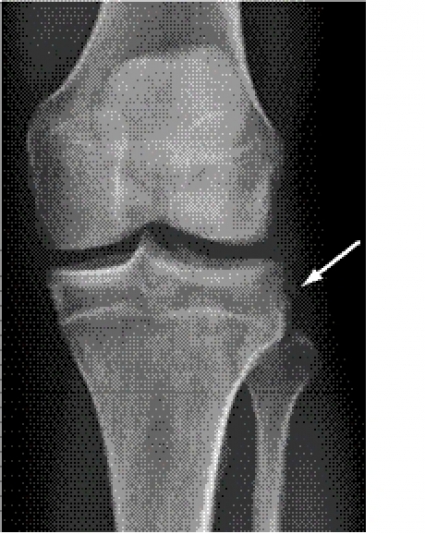

Slätröntgen. Vid akuta knäskador är en röntgenundersökning oftast negativ. Inte desto mindre är den viktig vid bekräftad eller misstänkt hemartros för att upptäcka frakturer. Både det främre och det bakre korsbandet brister ibland, med avulsionsfragment från tibia. Det sker oftast i yngre ålder på grund av att den relativa hållfastheten i ligament då ofta överskrider den i ben. Det bakre korsbandet, som är mycket starkare än det främre, kan dock brista med ett avulsionsfragment även i vuxen ålder.

En sk Segondfraktur är ett skalformat benfragment indikerande en avulsion av den främre delen av laterala ledkapseln från tibia och möjligen också de främre delarna av tractus iliotibialis [2]. Detta fynd är starkt associerat med främre korsbandsruptur. En avulsionsfraktur av processus styloideus fibulae, där bicepssena och kollateralligament fäster, kallas för »the arcuate sign«. Det är oftast associerat med bakre eller främre korsbandsskada och skador på posterolaterala ligamentkomplexet samt ett benmärgsödem i mediala femurkondylen. [3]. Slutligen förekommer osteokondrala ledytefragment, avslagna från patellas undersida eller från laterala femurkondylens utsida, i samband med patellaluxationer.